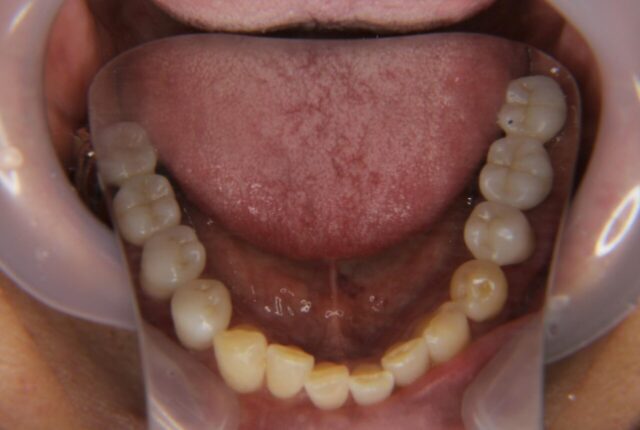

Before